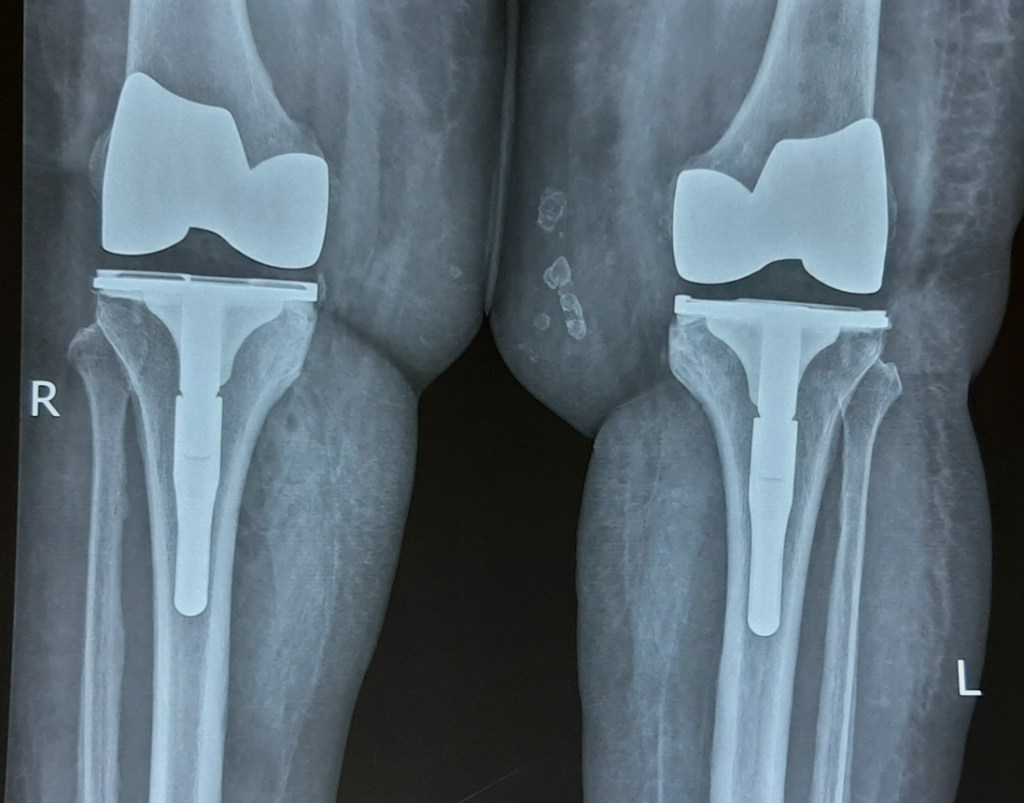

Total Knee Replacement is one of the most commonly performed orthopedic surgery. It involves replacing the articular surfaces (femoral condyles and tibial plateau) of the knee joint with smooth metal and highly cross-linked polyethylene plastic. It helps to relieve pain and restore function in severely diseased knee joints.

With modern pain management protocols, small incisions and use of Computer Navigation, recovery is very fast after knee replacement. Patients are mobile very next day.